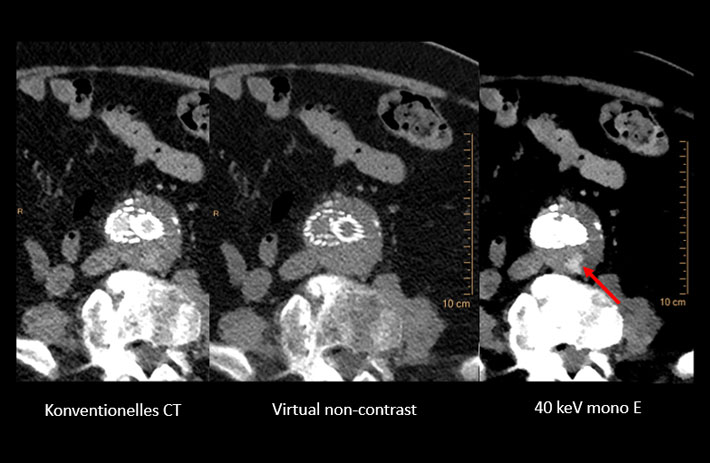

Mit dem Spektral-Detektor-CT werden Spektraldaten automatisch bei jedem Scan erfasst. Die Informationen stehen jederzeit auf der Scankonsole, der CT-Workstation sowie an jedem PACS-Arbeitsplatz zur Verfügung, sodass es nicht notwendig ist, den Patienten erneut zu scannen, bspw. wenn initial zufällige Anomalien festgestellt wurden. Dadurch profitieren Anwender durch eine höhere Diagnosesicherheit und weniger Nachuntersuchungen auf anderen bildgebenden Systemen. Unsere Fallsammlung zeigt, welchen klinischen Mehrwert der Spektral-Detektor-CT in unterschiedlichsten Anwendungsbereichen in der klinischen Routine bringt. Jede Woche gehen neue Fälle live.